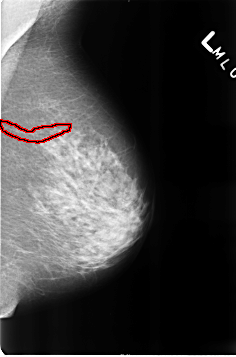

FILE: B_3254_1.RIGHT_MLO.OVERLAY

TOTAL_ABNORMALITIES 2

ABNORMALITY 1

LESION_TYPE CALCIFICATION TYPE VASCULAR DISTRIBUTION N/A

ASSESSMENT 2

SUBTLETY 3

PATHOLOGY BENIGN_WITHOUT_CALLBACK

TOTAL_OUTLINES 1

BOUNDARY

ABNORMALITY 2

LESION_TYPE CALCIFICATION TYPE LUCENT_CENTER DISTRIBUTION N/A